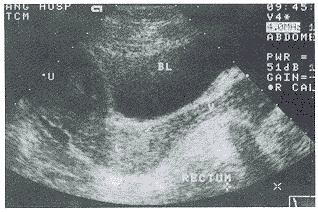

RC的超声诊断标准和分度的探讨:我们观察测量50例正常男女性仰卧位直肠声像图表现:在直肠肛管交界处前方可有1~10mm深的前突(图2),因此我们将≥10mm者列入异常统计。在临床治疗中,为了明确病变的严重程度,我们进行了分度的探讨。在观察中,我们发现症状严重者突出深度越深,而长度变短或变化不大,因此考虑以深度作为分度代表其严重程度。即前突深度10~20mm为轻度,21~30mm为中度,≥31mm为重度。本组轻度8例,中度13例(图3),重度3例(图4)。这种以深度为准的分度方法经临床观察、治疗是可行的。一般轻度者可采用中药治疗,中度以上可手术治疗,该分度法我们将在今后的工作中进一步研究探讨其可行性。

Reclum:直肠,V:阴道,BL;膀胱,U:子宫

图4 重度RC